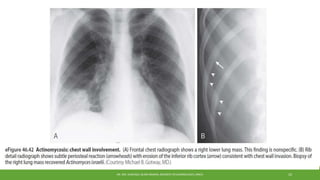

Imaging

•Classic finding for actinomycosis is direct extension of a cavity or mass through

an interlobar fissure.

•Commonly, changes are confined to a single lobe with consolidation, nodules,

one or more small cavitary lesions.

•Pleural thickening or effusions are also encountered.

•Advanced cases, the findings may be more distinctive, with penetration

through the chest wall and/or destruction of adjacent bone tissue.

•CT imaging may reveal bone erosion.